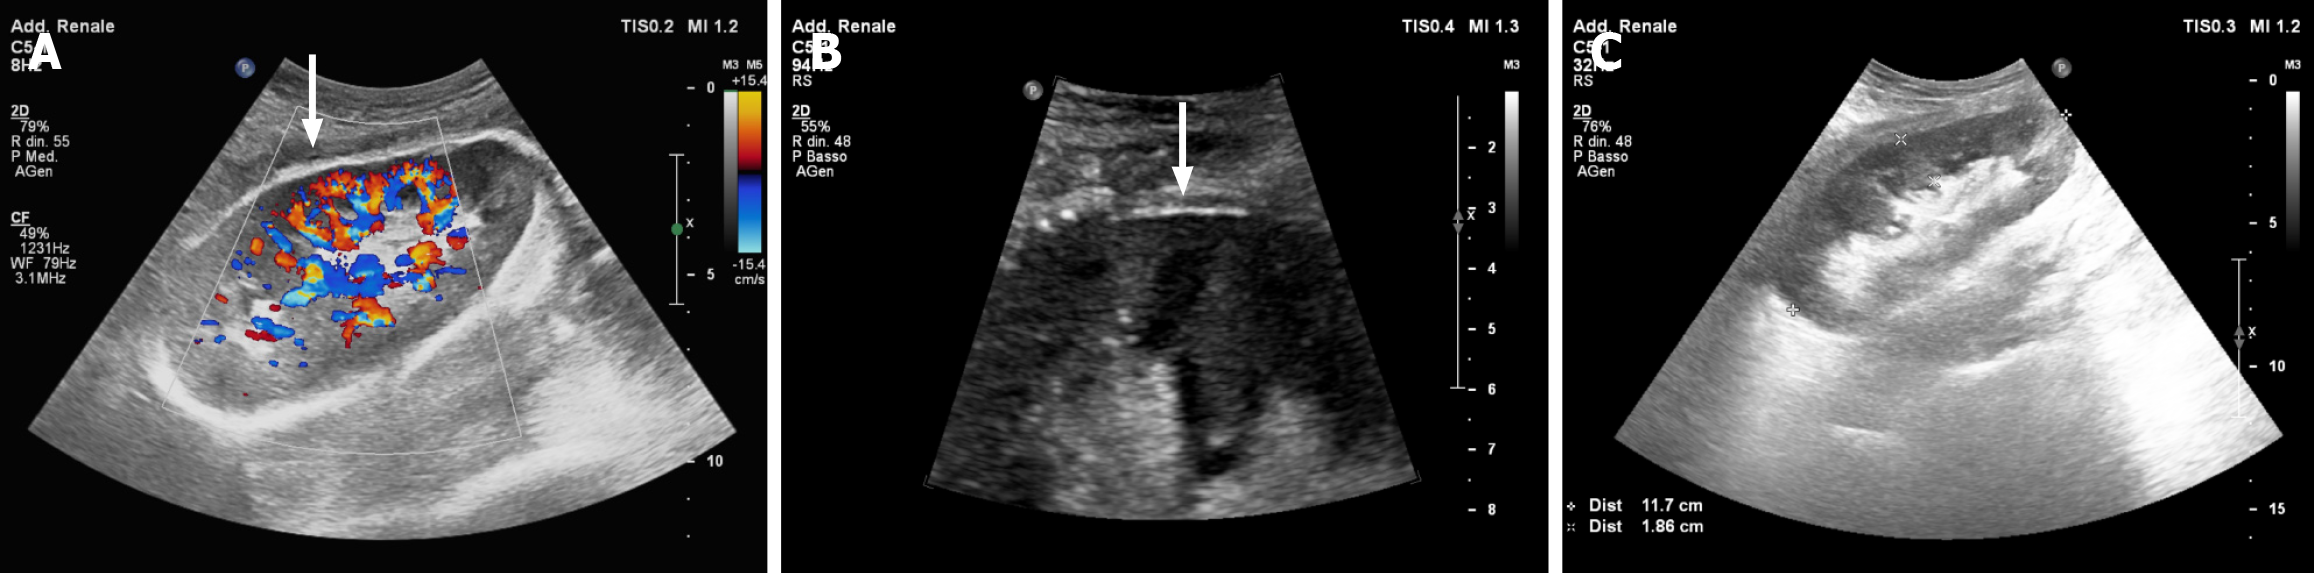

After a brief bedside assessment with a Doppler ultrasound (US) scan (showing a well-perfused graft surrounded by a large retro-peritoneal fluid collection), the recipient underwent immediate contrast-enhanced computed tomography (CT) evaluation. The imaging study demonstrated a large (9.6 cm × 4.3 cm × 17 cm), retro-peritoneal hematoma (Figure 1A) with features of active bleeding from the upper pole of the transplanted kidney (Figure 1B). A focal laceration of the renal cortex not involving the calyceal system and a 3.8-cm-wide area of parenchymal hypoperfusion were noticed in proximity to the blushing spot (Figure 1C). Therefore, a plan was made for surgical exploration.